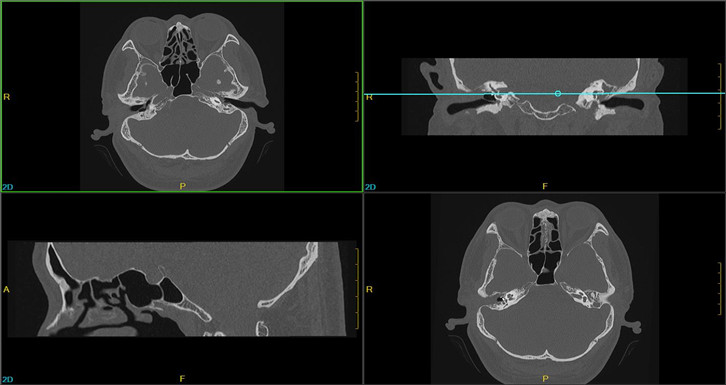

·0.275mm ultra-thin layer scanning can clearly show the fine structures in the human body, such as inner ear and small pulmonary nodules

Clinical Gallery